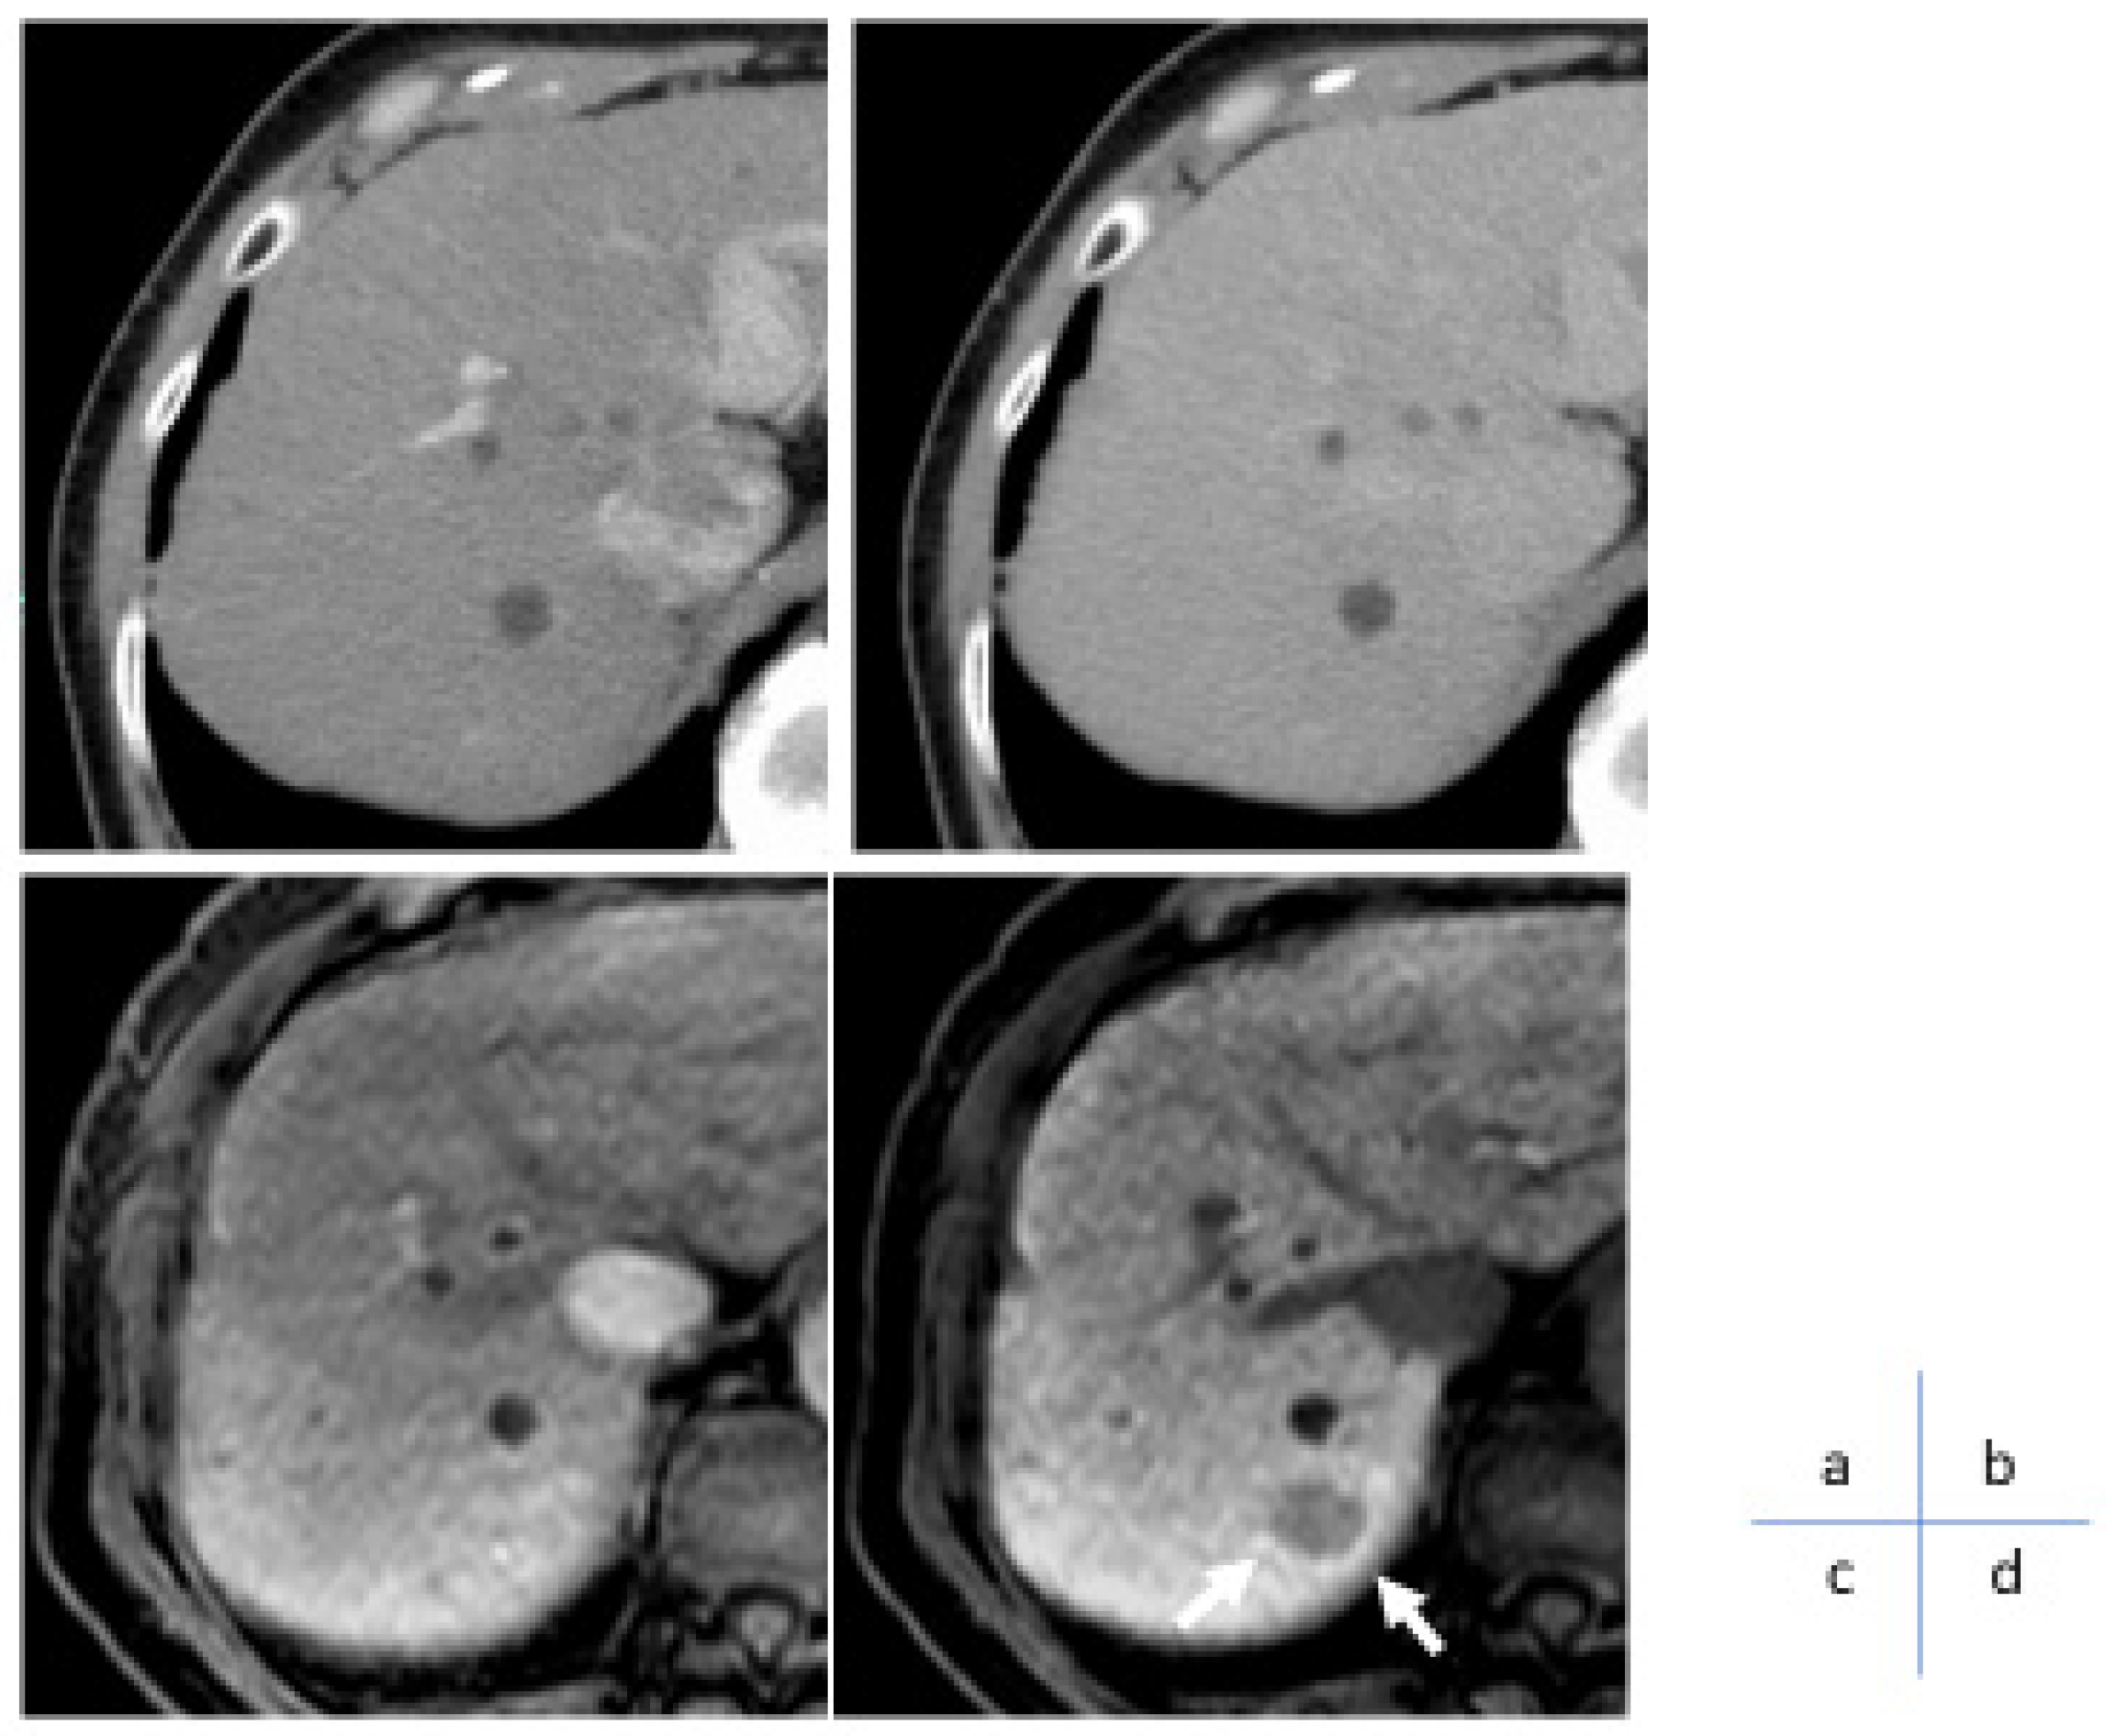

3. Role of Dynamic CT/MRI in Differentiating Tumor Grades

5. Dynamic CT/MRI Imaging for Predicting Response to Systemic Chemotherapy in HCC